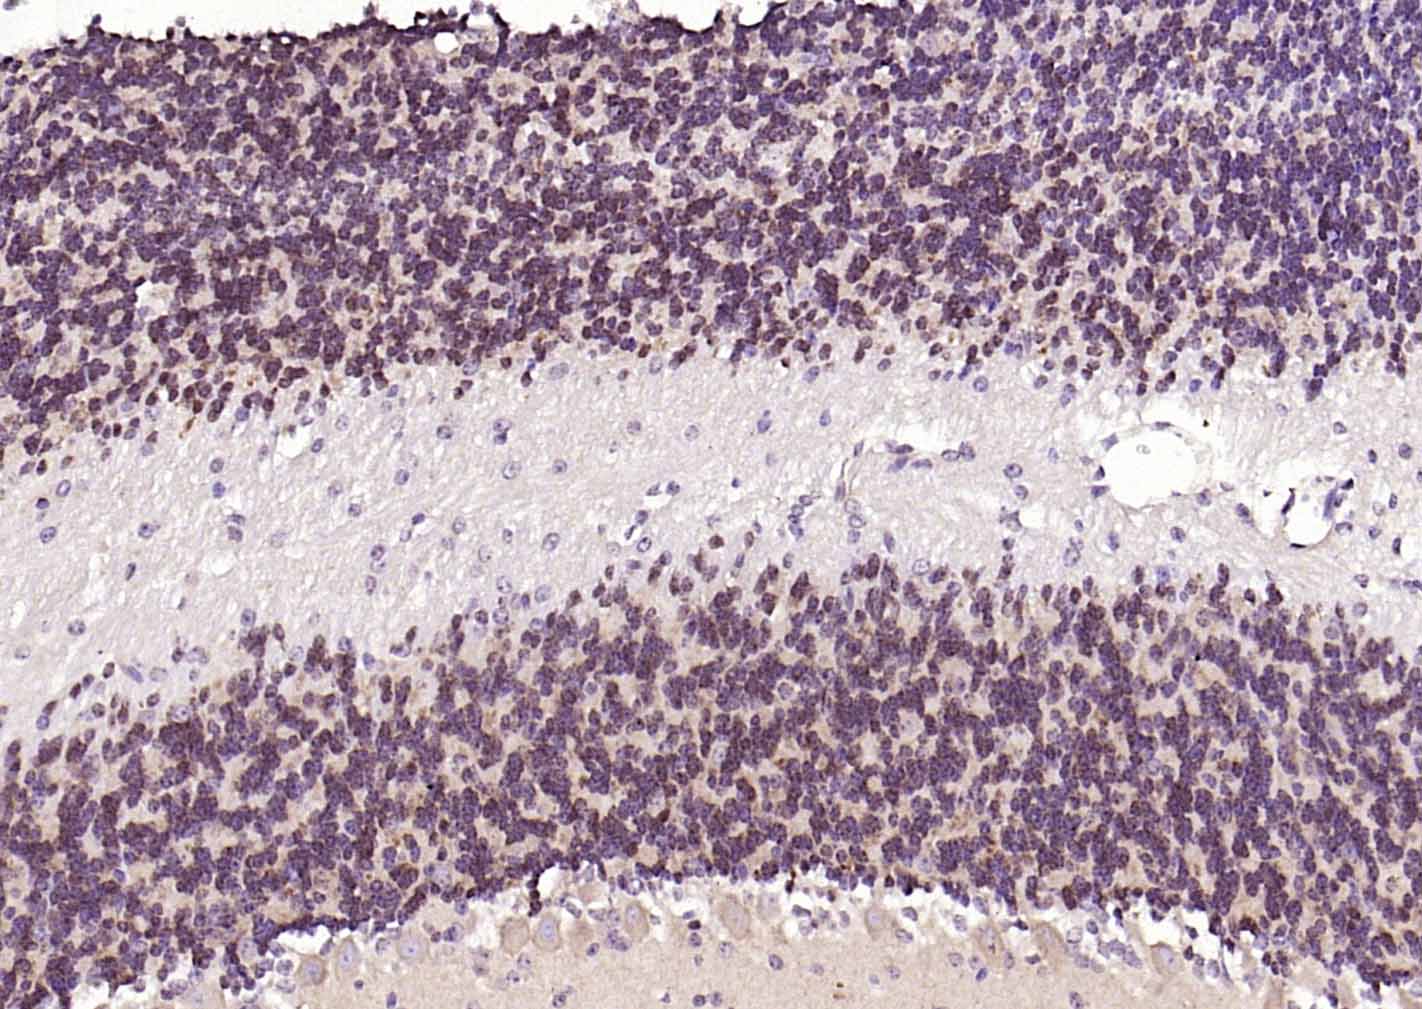

| IHC-P | Mouse, Rat | Human, Cow, Dog, Horse | 1:100-500 |

| IHC-F | Mouse, Rat | Human, Cow, Dog, Horse | 1:100-500 |